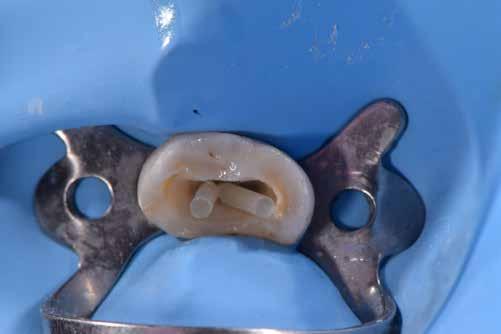

3. kép: Gyökértömés utáni állapot, gingivális ládaemelésre is szükség lesz. Tág, aszimmetrikus, meggyengített gyökércsatornák láthatók.

A gyökérkezelt fogak megerősítése, a restaurátum-fog komplexum sikerességének és túlélésének növelése a mai napig központi kérdéskör mind a restauratív fogászatban, mind az endodonciában. Ez utóbbinak az oka abban keresendő, hogy az endodonciai kezelés nem tekinthető teljesen befejezettnek, amíg a fog végleges koronai restaurátummal nincs ellátva. Sőt, vizsgálatok arról számolnak be, hogy azon fogak, amelyek a gyökértömést követő 4-6 hónapon belül lettek véglegesen restaurálva, nagyobb sikerességet mutatnak, mint amelyek ennél csak hosszabb idő elteltével (1). A gyökérkezelt fogak gyengüléséhez számos tényező hozzájárul, többek között: trepanálás és hozzáférési nyílás kialakítása, a dentin dehidratációja, a dentin struktúrájának átalakulása, az átöblítő-szerek erodáló hatása, az esetlegesen használt kálcium-hidroxid lágyító hatása stb. (2). A fenti okok miatt a gyökérkezelt fogak gyakrabban szenvednek el fatális kimenetelű töréseket, mint a hasonló kavitással rendelkező, de vitális fogak. Jelen tudásunk szerint ez idáig a legfontosabb gyengítő tényező a caries vagy korábbi trauma miatt kialakult koronai keményszövet veszteség, amelyet a terápiánkhoz szorosan kapcsolódó trepanálási folyamat tovább súlyosbít. Így kiemelten fontos, hogy a gyökérkezelt fogakba készülő restaurátumnak nem csak a hiányzó fogstruktúrát kell esztétikailag és funkcionálisan helyreállítani, hanem a meggyengült fogat is meg kell erősíteni, mintegy egységet alkotva a megmaradt zománccal és dentinnel. A gyökérkezelt fogak restaurálására bevett módszer volt a fogak „belső sínezése”, csapok segítségével. Ez a mai, modern esztétikai fogászati érában üvegszálas csapok segítségével történik. Ugyanakkor mind a vizsgálatok, mind saját klinikai tapasztalatunk, eddigi kudarcaink rávilágítottak arra, hogy az üvegszálas csappal való helyreállítás nem nyújt mindig ideális és időálló eredményt, valamint nem minden típusú fog esetén segít (2). A csapozás létjogosultságának eldöntésekor nem elegendő pusztán a megmaradt koronai fogmennyiséget vizsgálni, hanem figyelembe kell venni, hogy mely régióban helyezkedik el a fog, mekkora, és milyen irányú erők lépnek fel itt elsődlegesen, valamint a páciensnél várható-e extrém nagyságú erőbehatás (bruxálás, szorítás, parafunkciók stb.). Ha mindezeket figyelembe vettük, és az üvegszálas csap behelyezése mellett döntöttünk, akkor a következő problémákkal kell szembenéznünk: 1. A csap nem az eredeti állapotot állítja helyre biomechanikai szempontból, ugyanis a gyökércsatornában a fog tengelyében (ahol a csap lesz) nem lép fel terhelés ép fog esetén, helyette a gyökércsatorna falain jön létre és összpontosul a terhelés. 2. Az ovális, nem körszimmetrikus gyökércsatornában a csap nem fog megfelelően illeszkedni, vagy csak apikálisan (1. kép). 3. A kritikus cervikális területen, ahol a legtöbb stressz lép fel, a csap-ragasztócement arány nem ideális (a cement dominál), (1. kép). 4.A nagy mennyiségű ragasztócement könnyen tartalmazhat buborékokat, melyek később a cement megrepedését okozhatják. 5. A hagyományos üvegszálas csap nem köt össze megbízhatóan a ragasztó és/vagy csonkfelépítő anyagokkal, amely könnyen vezethet a csap megmozdulásához.